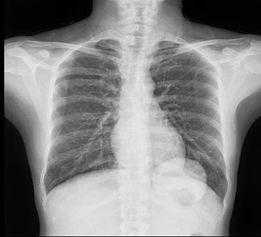

胸部X线片是肺隔离症影像学诊断的基本筛查方法。

它可以是这样的↓↓↓

图5左下肺野可见团块状密度增高影

也可以基本啥都没有↓↓↓

图6两肺纹理增多,左下肺见少许条索影,两肺门增浓

临床上常用胸片对肺内有无占位性病变进行初筛,但因其不能显示异常滋养动脉血管,无法对疾病进行定性诊断,常与肺部其他病变相混淆,临床诊断价值有限。